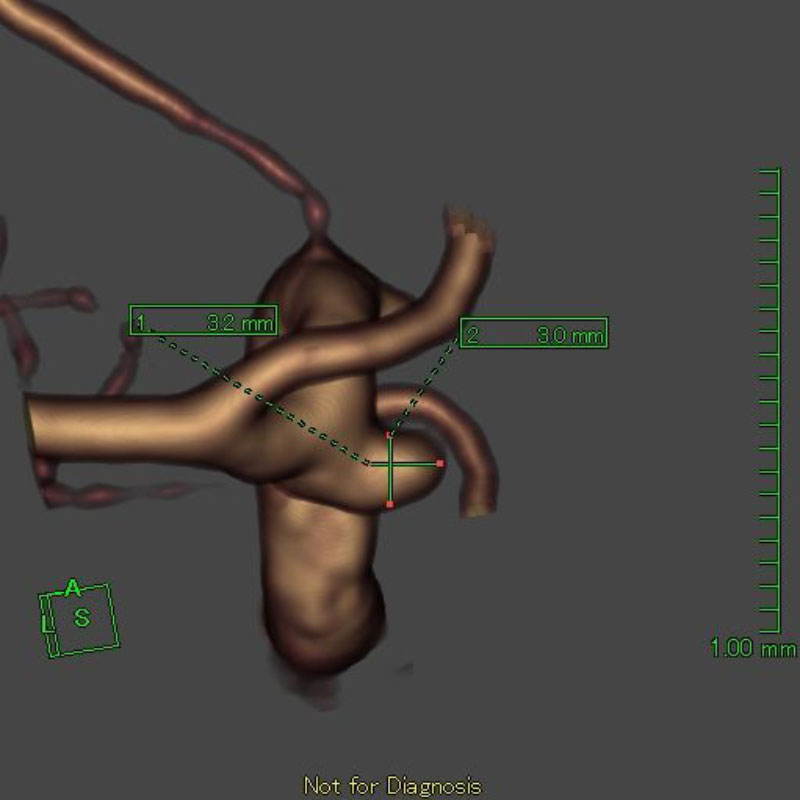

4

'25年1月

40代

右中大脳動脈瘤

クリッピング術

手術前

クリップ前

クリップ後

術後血管撮影